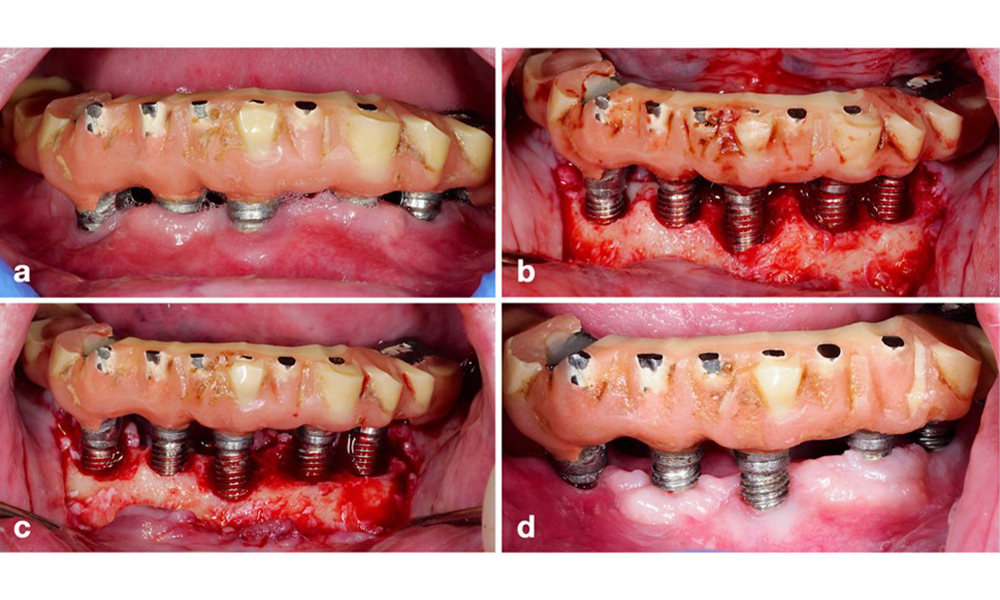

The prosthetic restoration should be removed during both non-surgical and surgical treatment to improve access to the implant surface. The choice of surgical intervention (e.g., resective, reconstructive, or combined) depends on several factors: (1) defect morphology (e.g., horizontal, dehiscence, intra-osseous, or combined) (figure 10), (2) implant surface (i.e., turned or modified/”rough”), and (3) presence or absence of sufficient keratinised and attached mucosa.

A resective approach (i.e., gingivectomy and/or apically positioned flap, with/without bone re-contouring) should be chosen in cases with mainly horizontal bone loss or wide defects, where the potential for bone regeneration is limited (figure 11).